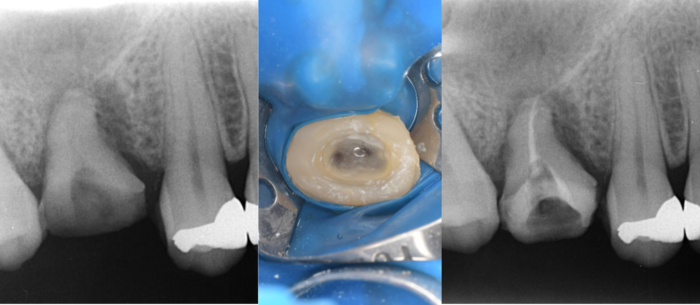

初診時デンタルX線写真

初診時CT画像

初診時デンタルX線写真とCT画像。

根管外に不透過像とそれを取り囲む透過像を認める。

コアを除去すると、分岐部へつながるパーフォレーションを認めた。

これが排膿の原因であったため、保存は困難と判断した。